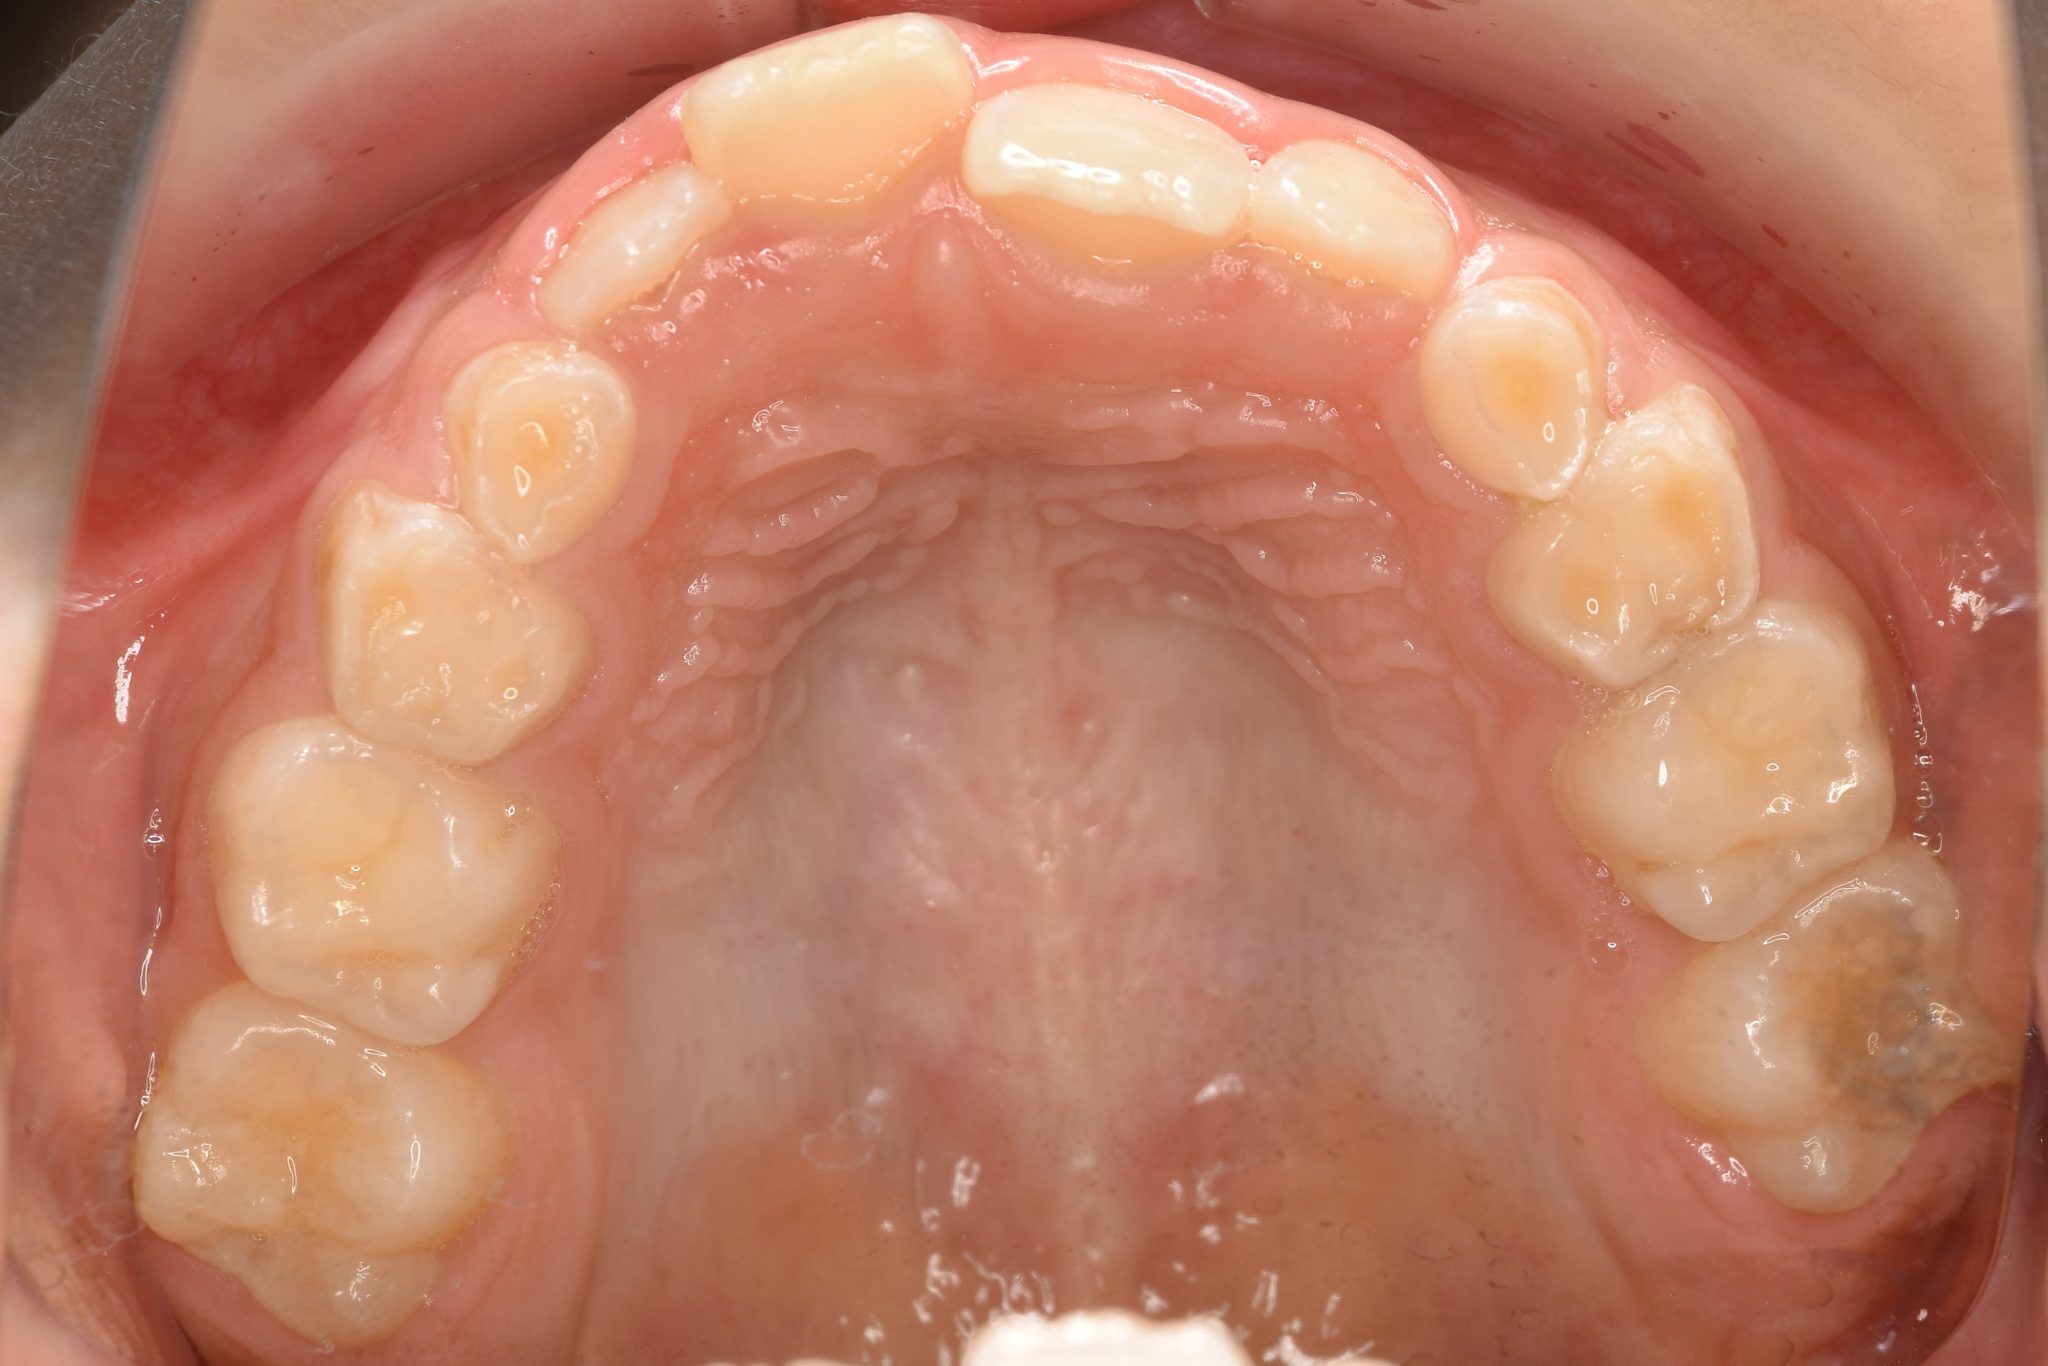

ビフォー

全顎ワイヤー矯正 症例_108

主訴 受け口|前歯がかみ合わない|顔貌

施術内容 小児矯正1期治療

治癒期間 3年11ヶ月間

費用 498,960円(税込)